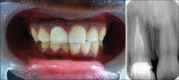

Anterior tooth fracture as a result of traumatic injuries, is frequently encountered in endodontic practice. Proper reconstruction of extensively damaged teeth can be achieved through the fragment reattachment procedure known as "biological restoration." This case report refers to the esthetics and functional recovery of extensively damaged maxillary central incisor through the preparation and adhesive cementation of "biological post" in a young patient. Biological post obtained through extracted teeth from another individual-represent a low-cost option and alternative technique for the morphofunctional recovery of extensively damaged anterior teeth.